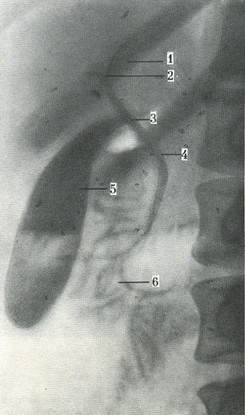

Холеграммы містять тінь не тільки міхура, але і жовчних проток. Протоки печінки виявляються через 5-15 хв, а жовчний міхур - через 30 хв після введення контрастної речовини (рис. 272). На цих знімках контури всіх проток рівні, тінь рівномірна. Крім оглядових холеграмм, можна зробити ряд серійних знімків, на яких вдається простежити послідовність заповнення контрастною речовиною проток і жовчного міхура.

![]() 272. Оглядова рентгенограма жовчних шляхів при холеографии (по Л. Д. Линденбратену). 1 - лівий печінковий проток; 2 - правий печінковий проток; 3 - печінковий проток; 4 - загальний печінковий проток; 5 - жовчний міхур; 6 - контрастна речовина в низхідній частині дванадцятипалої кишки.  |